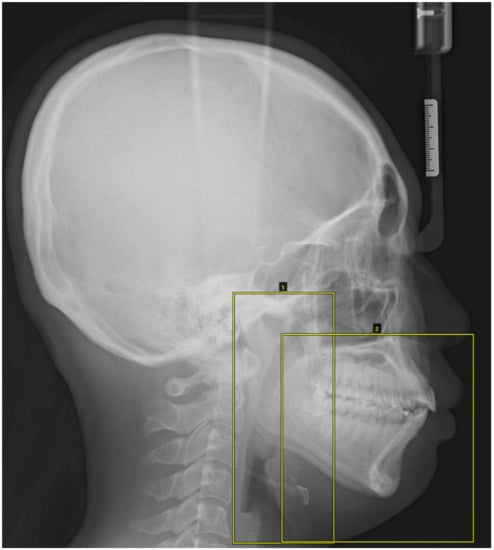

The lateral cephalometric images were labeled with two square markers: a left long square containing the condylar process, coronoid process, mandibular ramus, and airway space and a right square containing the dentoalveolar region, maxilla, mandibular body, and lower facial soft tissue (Figure 2).

Figure 2.

The lateral cephalometric images were masked with two square markers: a left long square containing the condylar process, coronoid process, mandibular ramus, and airway space and a right square containing the dentoalveolar region, maxilla, mandibular body, and lower facial soft tissue.